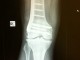

Arthroscopy is a type of ‘minimally invasive’ surgery. The surgeon is able to perform an inspection and surgical procedures using specialised instruments inserted through small incision in the skin. Where indicated, this minimizes scars and pain, and improves recovery in the early period following the surgery.